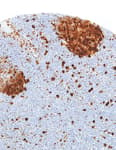

Mouse anti-PCNA Monoclonal Antibody, Purified [PC10]

Bethyl Laboratories Catalog # A500-024A A500-024A-T A500-024ACF

ValidatedDocuments (8) Citations ()Mouse anti-PCNA Monoclonal Antibody, Purified [PC10]

Validation Performed

All Bethyl Laboratories® antibodies are validated to meet our strict performance standards.

Target: PCNA

Reactivity: Human, Mouse

Applications:

Platforms: COMET™

Host: Mouse

Conjugate:

Purity:

For ordering information, see our International Distributors

Product has been discontinued